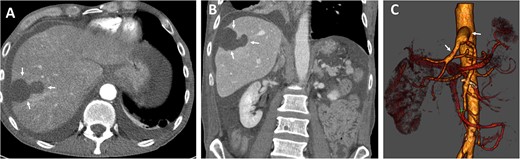

The oral antibiotics were administered and continued for another 10 days, and the patient was discharged on the 12th postoperative day in good general condition, fully mobilized, free of fever and infections. Follow-up CT showed a stable hepatic lesion (Fig. 4).

Follow-up (46 months after liver infarction) axial (A) and coronal (B) CT angiographic images demonstrate a stable hepatic infarction lesion 33 × 18 × 20 mm (arrows).